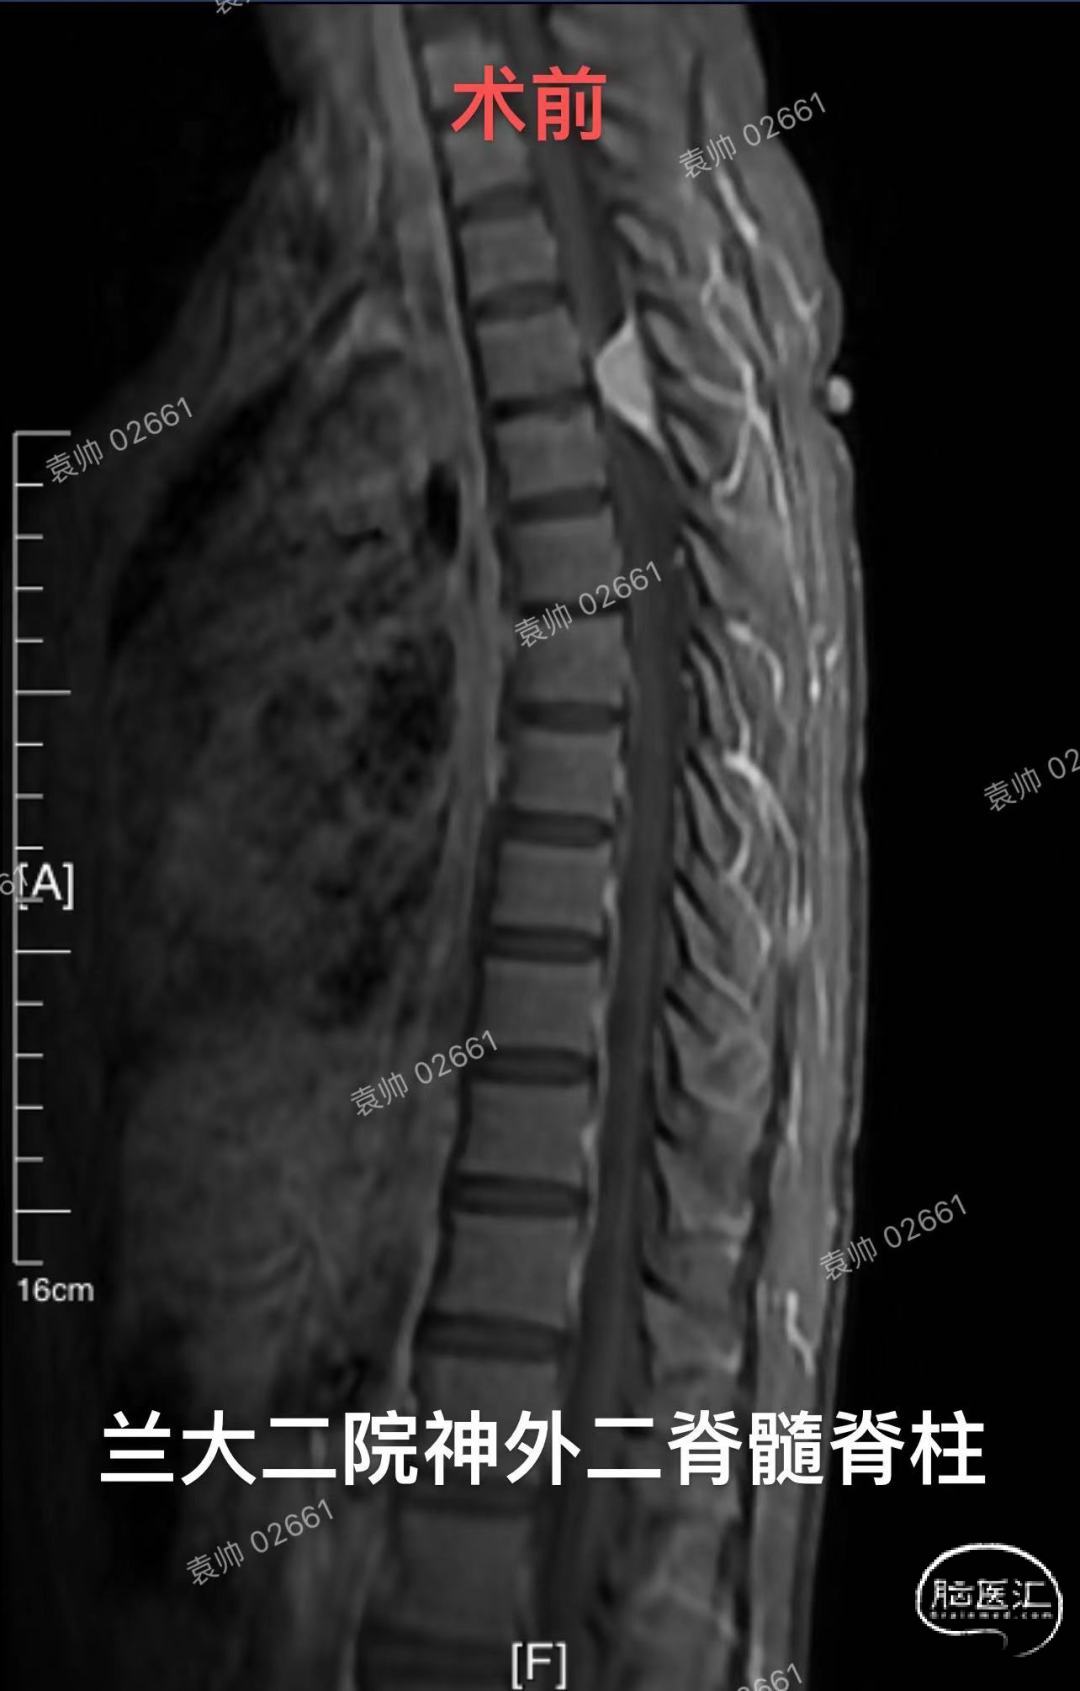

兰州大学第二医院神经外科二病区脊髓脊柱组病例分享:20岁年轻女性,T3-4脊髓背侧脊膜瘤。对于胸段脊膜瘤的治疗,大家都不陌生,手术难度不大,术后复发率低。但是相对于大多数凸面脑膜瘤,可以做到肿瘤基底硬膜全切,达到Simpson 1级切除,脊膜瘤全切附着硬脊膜,重建困难,容易术后脑脊液漏,并且对于年轻患者,不能完全避免肿瘤复发。由于硬脊膜内外层易于剥离,不同于硬脑膜,而脊膜瘤通常只会侵及内层硬膜,所以,我们推荐使用Saito技术,以剥除肿瘤附着硬脊膜内层,达到近似Simpson 1级切除的效果,可以有效预防肿瘤复发。